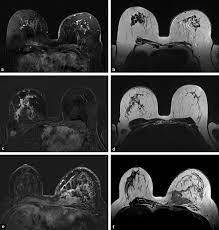

When the cancer grows into the rest of the body through the blood vessels and lymph vessels, breast cancer spreads. Inflammatory breast cancer occurs when cancer cells block the lymphatic vessels in skin covering the breast, causing the characteristic red, swollen appearance of the breast. Inflammatory breast cancer inflammatory breast cancer is a rare type of breast cancer that develops rapidly, making the affected breast red, swollen and tender. A breast mri usually is performed after you have a. The usual cause of inflammatory breast symptoms is breast mastitis or duct ectasia.

The features of a malignant breast condition on mri scan are often to do with the outer irregular borders of a lesion. Inflammatory breast cancer affects breast tissue and can appear unusually dimpled or thick. Absence of lump or breast mass in a patient suffering from an inflammatory skin condition of the breast, suggests the presence of skin or subcutaneous inflammatory condition caused by either infection or inflammatory breast cancer. The skin looks like the skin of an orange, and may be discolored with painful and itchy breast. The breast is enlarged (often of relatively short onset), indurated, erythematous, warm, and may be tender and painful. But not every woman who has been diagnosed with breast cancer needs a breast mri. What does breast cancer look like on a mammogram? A lump in the breast. Breast mri is sometimes used in women who already have been diagnosed with breast cancer, to help measure the size of the cancer, look for other tumors in the breast, and to check for tumors in the opposite breast. Most cases are invasive ductal carcinomas, which develop in the cells lining the milk ducts and spread throughout the breast. The breast can also be painful in inflammatory breast cancer, but this is not always the case. Evaluating the impact of preoperative breast magnetic resonance imaging on the surgical management of newly diagnosed breast cancers. When the cancer grows into the rest of the body through the blood vessels and lymph vessels, breast cancer spreads.

Inflammatory breast cancer is an an aggressive and fast growing breast cancer in which cancer cells infiltrate the skin and lymph vessels of the breast. They're often easy to move around (mobile) and may be tender. Ibc symptoms are caused by cancer cells blocking lymph vessels in the skin causing the breast to look inflamed. symptoms include breast swelling, purple or red color of the skin, and dimpling or thickening of the skin of the breast so that it may look and feel like an orange peel. Unlike traditional forms of breast cancer, inflammatory breast cancers do not develop unusual lumps within the affected breast. The skin is thickened and edematous, classically with a peau d'orange appearance. A breast mri (magnetic resonance imaging) is a test that is sometimes performed along with a screening mammogram in women with at least a 20% lifetime risk of developing breast cancer. What does breast cancer look like on a mammogram? Mri of breast can help breast cancer diagnosis. Inflammatory breast cancer inflammatory breast cancer is a rare type of breast cancer that develops rapidly, making the affected breast red, swollen and tender. A rash isn't the only visual symptom of inflammatory breast cancer. Inflammatory breast cancer (ibc) is rare, making up about 2 to 4 percent of breast cancer cases. Inflammatory breast cancer pictures and symptoms The skin looks like the skin of an orange, and may be discolored with painful and itchy breast.

It blocks the lymph vessels in the skin of your breast. They're often easy to move around (mobile) and may be tender. When the cancer grows into the rest of the body through the blood vessels and lymph vessels, breast cancer spreads. Breast lesions and chest wall abnormalities 8. Pitting, thickening, or dimpling of skin on the breast, so that it looks like an orange peel, a condition called peau d'orange. Most cases are invasive ductal carcinomas, which develop in the cells lining the milk ducts and spread throughout the breast. To help determine the extent of breast cancer: There may or may not be an underlying palpable mass. Mri of breast can help breast cancer diagnosis. Inflammatory breast cancer pictures show a red and/or swollen breast that appears inflamed. A breast mri usually is performed after you have a. J natl compr canc netw. If these tests don't answer the quest.